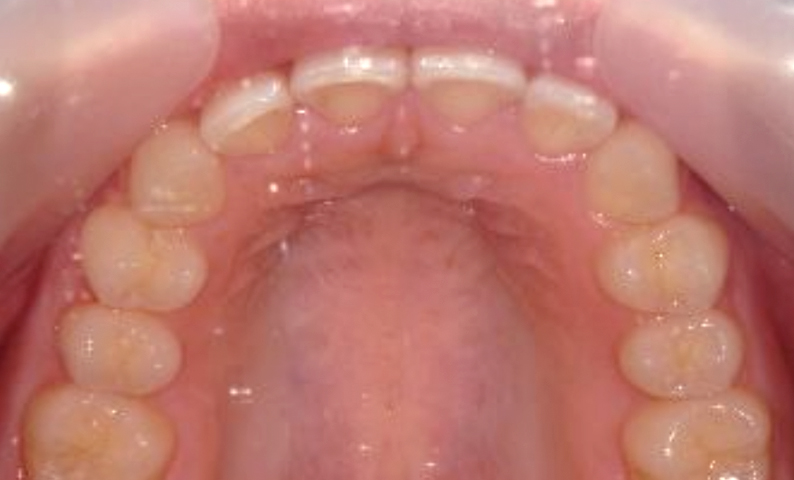

症例_001 上下顎の部分矯正

治療期間:12ヶ月金額:54万円+税女性前歯のガタガタ逆八の字